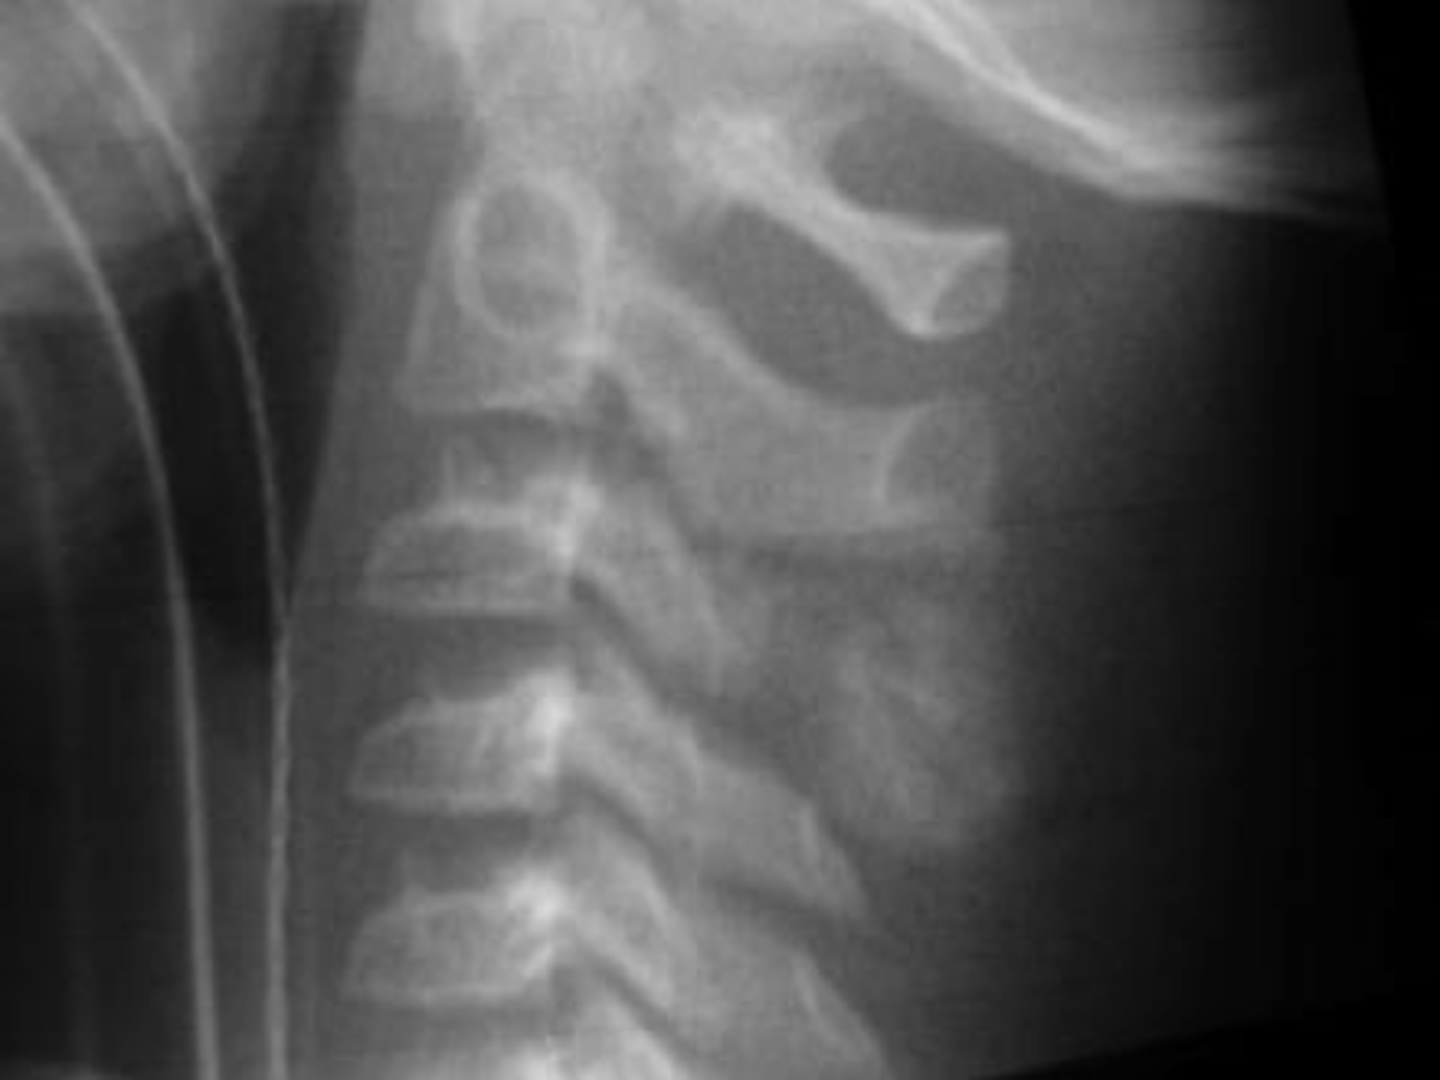

- Left: Paget Disease

- Middle: Vertebral hemangioma

- Right: Osteoporosis

Complete the DDx for vertebral hemangioma

<p>Complete the DDx for vertebral hemangioma</p>

- Vertical striations (corduroy cloth)

- Expansion (rare) may result in neurologic findings

- Skull ("sand dollar")

- Paravertebral swelling

State the radiographic features of vertebral hemangioma

<p>State the radiographic features of vertebral hemangioma</p>